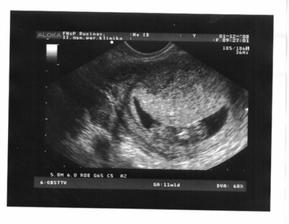

1.12.2008 - sme 11tt+1, krpček má 35 mm, prvykrat som videla ako sa vrti, nadherny pocit 🙂